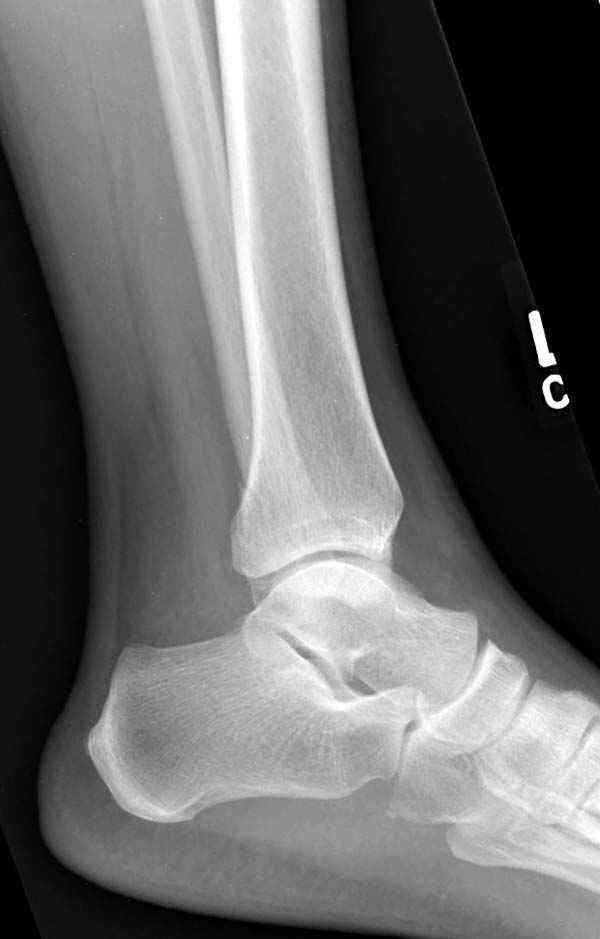

Случай прошлого года:пациентка-молодая ,крупная женщина ,30лет.Травма в начале апреля 2009г-пронационный перелом лодыжек с подвывихом стопы.Ко мне обратилась через 35 дней,прооперирована 22.05.2009г.Внутренняя лодыжка фиксирована по Веберу,наружная реконструктивной пластиной с наложением болта-стяжки.Иммобилизация "сапожок" в течении месяца,затем пригипсовано "стремя".Гипс снят 10.07.2009г

Достаточно быстрое восстановление функции.В октябре 2009г-почувствовала боль,в области рубца над гайкой открылся свищ.На Р-граммах-консолидация переломов и смещение гайки по стяжке.10.11.2009г-конструкции удалены,санация,заживление ран.В настоящее время пациентку ничего не беспокоит.На операции-раскручивание гайки-болталась на конце стяжки.Вопросы:какой механизм раскручивания и что я неправильно сделал?Свои версии:1)в области синдесмоза успела образоваться рубцовая ткань,которая при движении в суставе"пружинила",поскольку голеностопный сустав является спиральным, то и биомеханика подобна кривошипному механизму.2)Реконструктивная пластина не "реконструировалась" по форме лодыжки.Наложил,как есть.То есть подпружинивала сама пластина.Ну,это мои догадки.Что нужно,чтобы избегать впредь таких,пусть и не "страшных"осложнений:Рассверливать через лодыжку область синдесмоза?Ставить шайбу-гровер?Тщательно моделировать пластину?Прилагаю сравнительные снимки-сразу после операции и перед удалением конструкции.

Визуально никаких вопросов по репозиции не было.Да и на основании чего сомнения,что наружная лодыжка не полностью репонирована или прорезалась проволка ???Я не вижу...Снимок после репозиции справа.